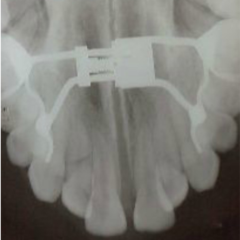

Topic: Expansion

• We are discussing expansion. I am sure, we all have done few. We will revisit protocol.

• There are also other types of expanders besides RPE and we will look intot hem as well.

• Narrow maxilla is indicative of expansion in presense of a crossbite however, expansion is being used as a corrective treatment in Class II and Class III cases as well. We will examine latest literature on the subject.